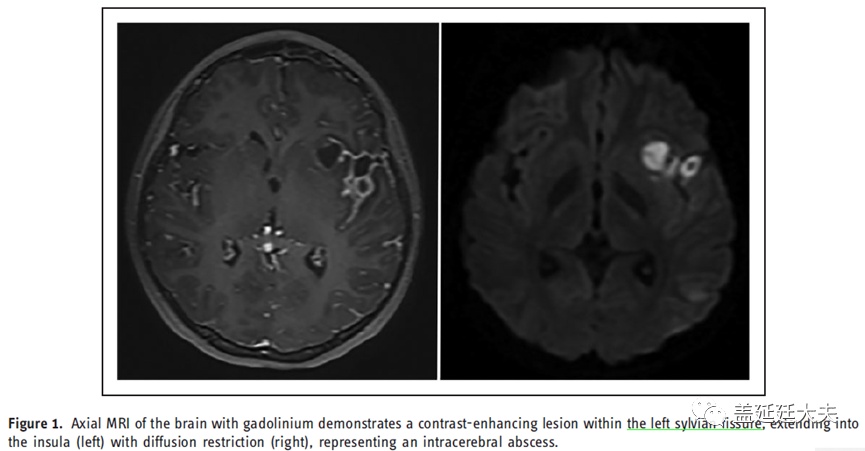

患儿10岁,女,主诉”头痛、嗜睡和发烧7天“。头颅MRI示左侧外侧裂、岛叶周围脓肿,感染源为副鼻窦炎(图1)。患儿接受广谱抗生素治疗,并接受两次内窥镜鼻窦手术和两次立体定向脓肿引流手术。细菌培养显示金黄色葡萄球菌和链球菌的生长。在住院的第18天,她突发左侧脑实质内出血伴小脑幕切迹疝,遂行急诊血肿清除和左侧颅骨去骨瓣减压术。